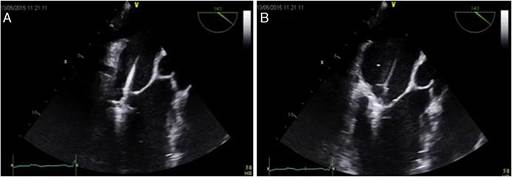

Mediante maniobras especiales y siempre guiado por el ETE se procede a pasar la válvula en forma perpendicular a la apertura de las valva a nivel del plano de unión A2/P2. El Eco tridimensional tiene su utilidad en este momento para direccionar la maniobra. Se pasa la válvula y se procede a capturar la valva ajustando el MitraClip. Después de corroborar el grado de insuficiencia por Doppler se procede a liberar el MitraClip. (Ver fig. 2).

Figura 2 El ecocardiograma transesofágico donde se muestra en: A) La posición del MitraClip abierto para atrapar ambas valvas de la mitral, y B) Ambas valvas han sido capturadas por el MitraClip y este es cerrado para determinar el adecuado cierre mediante

Se revisa mediante el ETE observado que quedó un flujo de regurgitación mitral importante por lo que se procede a colocar y liberar un segundo MitraClip, (ver fig. 3), con este último, la insuficiencia mitral se redujo de grado 4+ a una insuficiencia mitral mínima, por lo que se da por terminado el procedimiento con éxito. No se presentaron complicaciones.